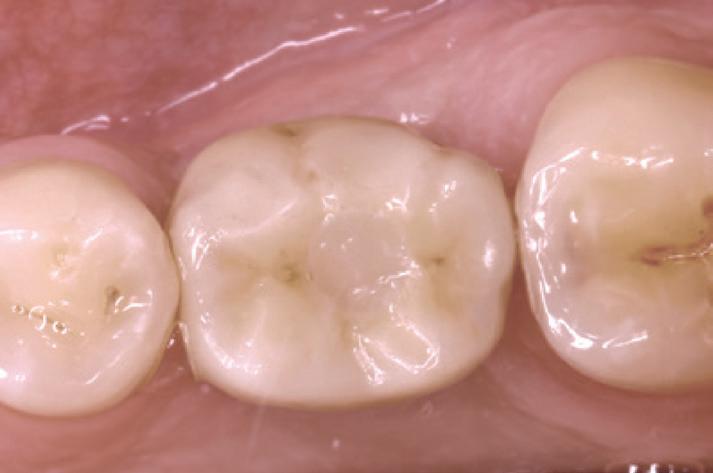

The Ivoclar Group is launching Tetric® plus, a new simplified composite specially designed to set new standards in universal composites. Tetric plus takes its name from the Greek prefix “tetra”, meaning “four” and this number is central to its key product features. It incorporates four essential elements: simplified shade matching with just 4 shades, increments of up to 4mm for greater efficiency, versatile application options in all 4 quadrants and an optimised 4-filler technology for excellent handling and aesthetic results.

Tetric plus revolutionises shade selection in dentistry, allowing for easy shade matching with its innovative colour cloud concept. Just 4 shades cover the entire spectrum of the classical VITA shades. Thanks to its exceptional shade adaptation, Tetric plus creates an outstanding chameleon effect: In its cured state, the material absorbs and scatters light in a way that closely mimics natural tooth structure, allowing it to blend almost seamlessly with the surrounding tooth structure. This high level of adaptation is achieved through the perfect combination of monomers, fillers and pigments.

Another remarkable feature of Tetric plus is its ability to accommodate variable layer thicknesses ranging from 0.1 to 4mm, allowing for greater flexibility while also reducing material consumption. Another notable advantage is its reliable curing time of just 3 seconds,1 that allows for a fast and easy application. These short curing times streamline workflows, minimise interruptions for dentists and enhance treatment efficiency. By enabling faster and more efficient restorations, Tetric plus not only saves valuable time but also improves the overall patient experience.

Tetric plus is a simplified universal composite that is suitable for all cavity classes, from Class I to V. With just one product, dentists can treat a wide range of indications in all 4 quadrants, significantly reducing material consumption and streamlining the workflow. For maximum handling convenience, Tetric plus is available in two viscosities: sculptable and flowable.

The quality of Tetric plus is defined by its innovative 4-filler technology, which integrates a combination of nano-

and micro-particles to deliver outstanding mechanical properties. Tetric plus ensures reliable curing for layers of up to 4mm while offering high radiopacity to facilitate accurate detection during diagnosis. The mechanical properties include high flexural strength (133 MPa), high compressive strength along with low wear and low shrinkage stress, reducing the risk of marginal gaps.

Tetric plus is more than just another composite: it is designed to simplify the daily workflow of dentists and optimise their treatment efficiency. With easy shade selection and short curing times, dentists can focus entirely on patient care, while delivering efficient and high-quality work. In summary, Tetric plus combines 4 shades with 4mm layer thicknesses, universal applicability in all 4 quadrants and an innovative 4-filler technology, making it the ideal solution for the demands of modern dentistry.